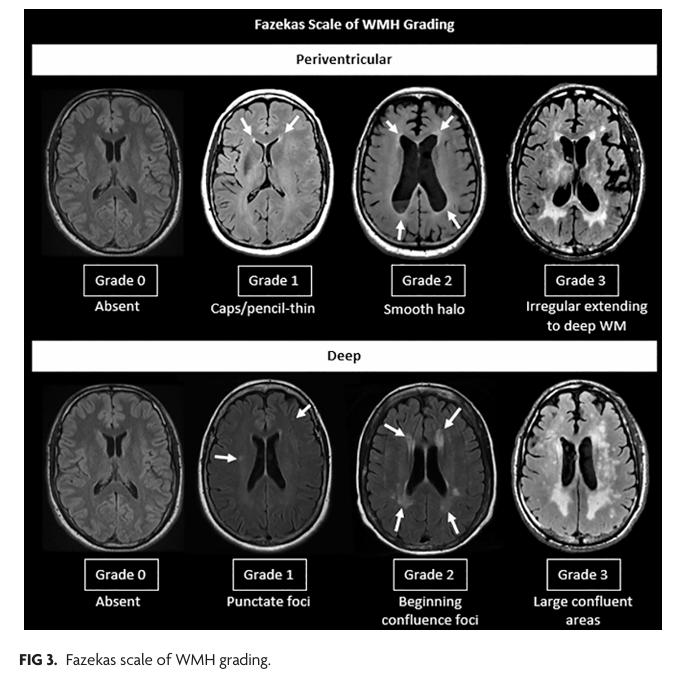

말씀하신 뇌실질에 하얀 병변은 소혈관질환이라고 합니다.

1. 미세 허혈(약한 혈관성 변화, 작은 백질변성)

– 고혈압·당뇨가 있는 경우 40대 후반~50대부터 서서히 나타날 수 있음

– 아주 초기 단계에서는 작은 점 형태로 보이기도 함

– 대부분 경미한 경우 임상적으로 큰 문제는 없지만, 장기적으로는 관리가 필요함

실제 판독에서는 같은 부위를 다른 시퀀스(T1, FLAIR 등)에서 비교해 미세허혈인지 정상 구조인지 판단합니다.

정식 판독문 확인 + 신경과 상담을 권합니다. 특히 판독에서 “소혈관병(small vessel disease)”, “white matter hyperintensity”, “미세허혈” 등이 언급되는지 확인하는 것이 좋습니다.